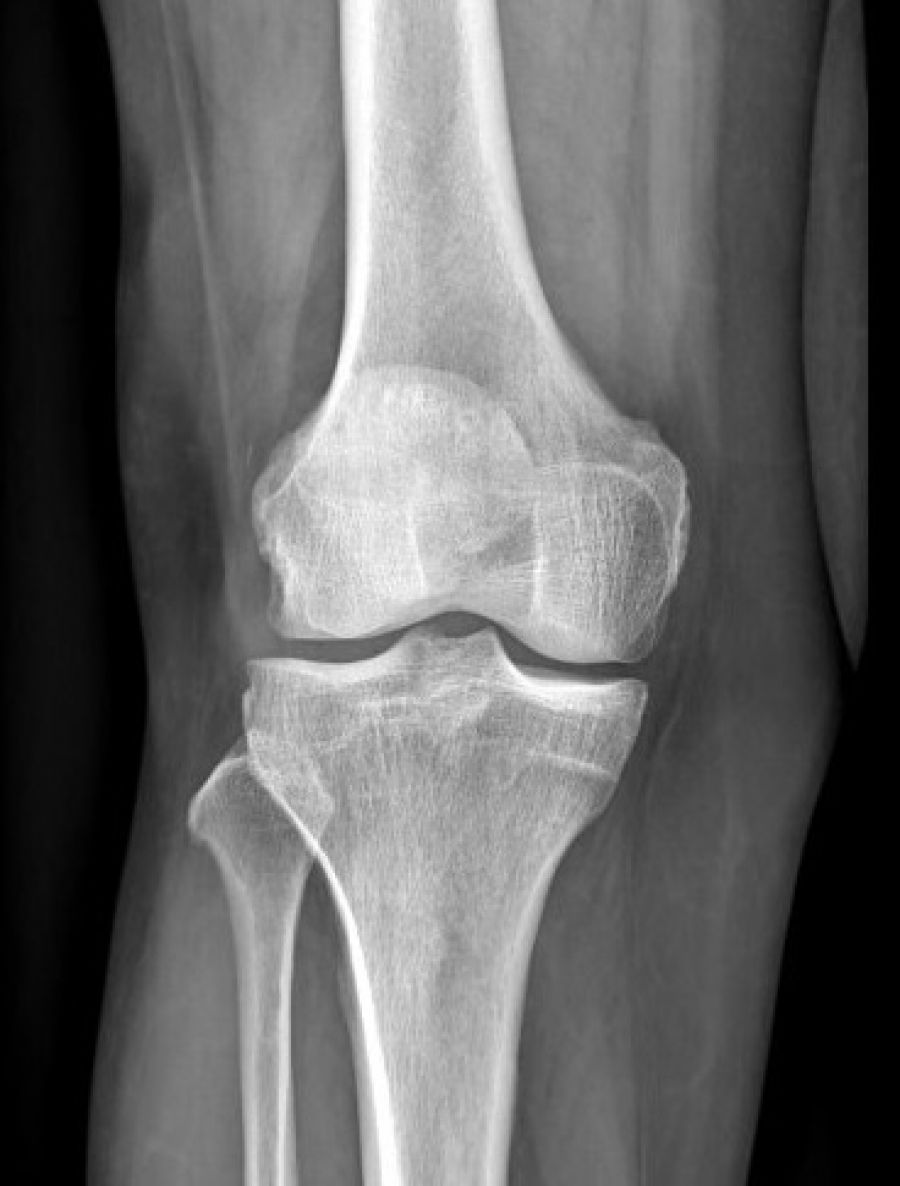

Les radiographies sont fréquemment requises entre autres, pour la recherche d'une fracture dans le cadre d'un traumatisme, les bilans d'arthrose, les bilans statiques, l'étude des poumons au cours d'une radiographie thoracique ...

Réaliser dans différentes positions selon les "incidences" utiles au diagnostic.